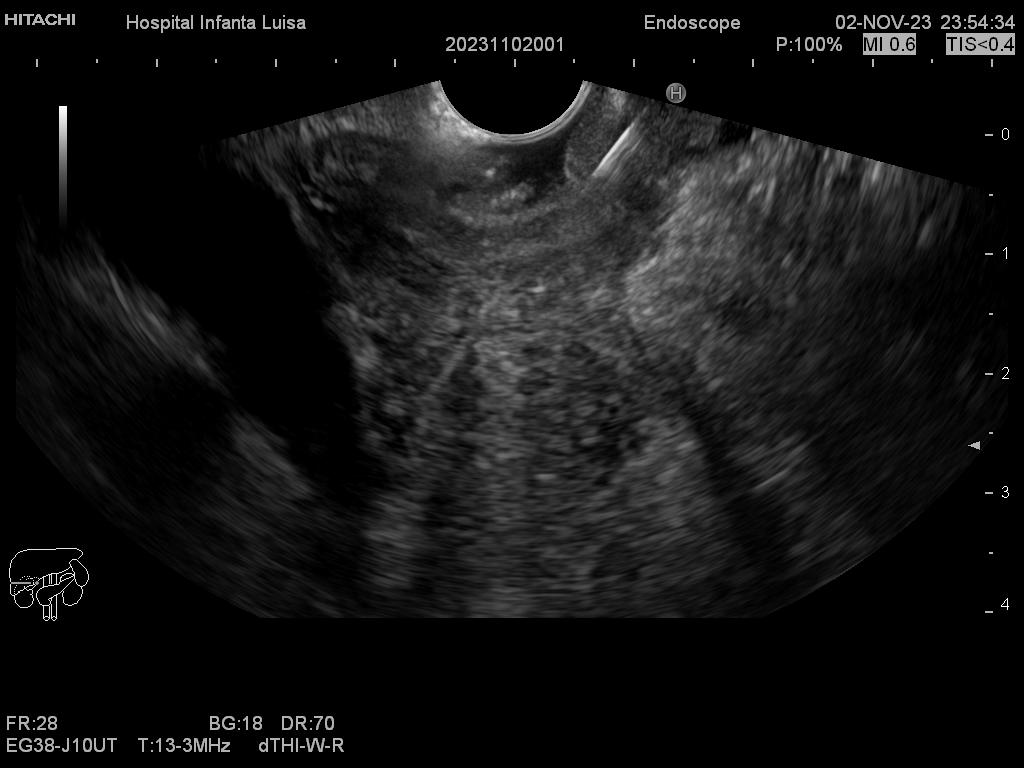

Mediante dicha exploración se explora minuciosamente los tramos mencionados, permitiendo valorar distintas patologías como lesiones propias de la pared de estos órganos (determinado su profundidad y extensión), o lesiones que quedan en órganos anexos, pero por fuera, de ahí la importancia de la visualización ecográfica, como páncreas, mediastino, hígado, diferentes adenopatías o masas indeterminadas previamente, entre otros.

Igualmente, es una técnica básica hoy día en el estudio de todo tipo de lesiones pancreáticas, en la determinación de formaciones subepiteliales esofágicas, gástricas (más frecuentes) o duodenales, o en el estadiaje de patología tumoral a estos niveles. La Ecoendoscopia permite la toma de biopsias a estos niveles, con control endoscópico y ecográfico, siendo una técnica de gran rentabilidad diagnóstica y seguridad.